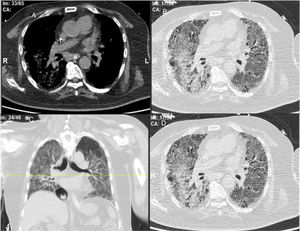

ResultsWe could include 230 patients (female 177 (77%) and males 53 (23%)) with established RA, fulfilling the 2010 ACR/EULAR classification criteria for RA.12 Their mean age was 47.06±11.75 years and disease duration 64.11±54.72 months. RF was positive in 101 (43.9%) and ACPA was positive in 220 (95.7%), while ANA was positive in 58 (25.2%), anti-Ro/SSA in 31 (13.5%), anti-La/SSB in 10 (4.3%), anti-RNP in 2 (.9%) and none of the patients showed anti-Sm antibodies. Anti-Jo-1 was positive in 5 (2.2%), none of them had increased CPK levels and all five cases showed typical erosive changes consistent with the diagnosis of RA (Fig. 1). Two out of the 5 cases with positive Anti-Jo-1 had ILD (Figs. 2 and 3). Detailed demographic features, clinical manifestations, laboratory investigations, SHS, drug therapy and disease activity scores are summarized in Table 1. In the controls (n=75), RF (low titer) was positive in 4, ANA was positive in two (2.7%), anti-Ro/SSA in three (4%), and none of the control group tested positive for anti-La/SSB, anti-Sm, anti-Jo-1, anti- U1RNP autoantibodies and none tested positive for ACPA.

An interesting finding in our study is the positive anti-Jo-1 in five (2.2%) patients, and two of them had aggressive ILD who can be classified as RA-ASS overlapping syndrome. Anti-Jo-1 correlated positively with ILD and RF titer. One patient had a high RF titer, negative ACPA and positive ANA, erosions typical for RA, positiveanti-Jo-1, while the other case was seropositive for RF, ACPA and ANA, typical erosions consistent with the diagnosis of RA and concomitant ILD and we classified the two cases with ILD as having RA-ASS overlap. Methotrexate (MTX) induced hypersensitivity pneumonitis cannot explain acute respiratory distress syndrome as observed in two of our patients with RA-ASS overlapping syndrome. First MTX induced hypersensitivity pneumonitis usually occurs in the initial weeks to months of starting treatment with MTX as acute drug reaction33; second no significant association was observed between MTX dose and ILD in our study (p=.701); third and most important it is not known that MTX can induce positive anti-Jo-1 autoantibodies which are now considered the hallmark diagnostic autoantibody in ASS.